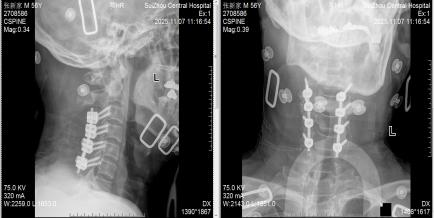

圖1:術(shù)前MRI見椎管內(nèi)積血壓迫脊髓

圖3:術(shù)后X線見內(nèi)固定位置良好